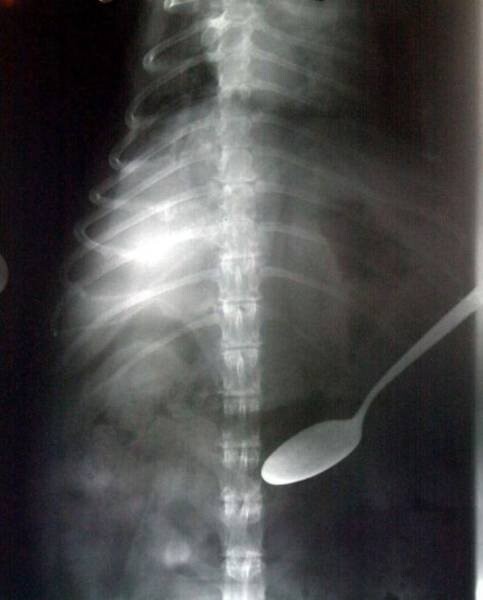

12. Ложка